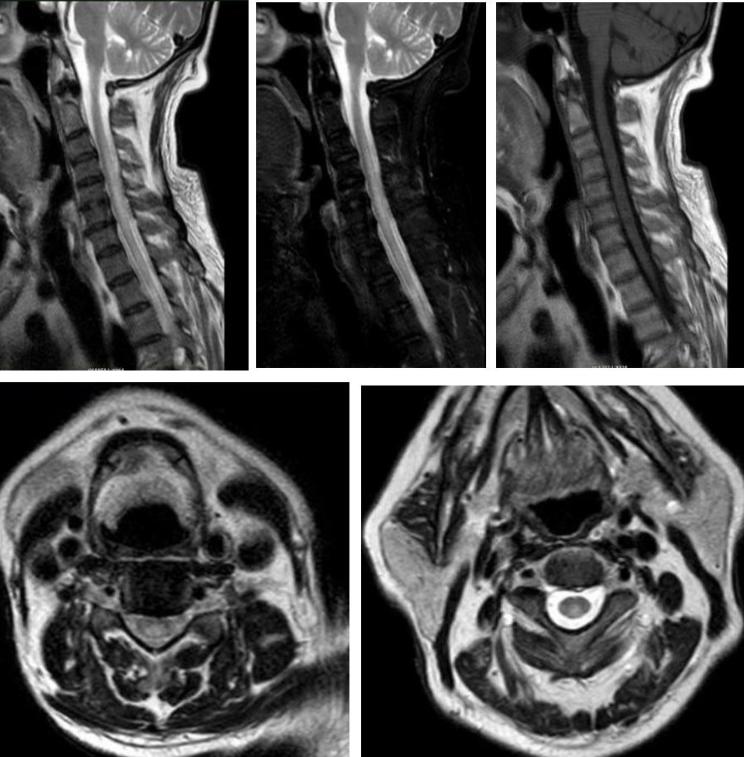

男性34岁,肢体麻木无力1月余入院。查体:神志清,双上肢肌力5级,双下肢4+级,远端4级,左上肢触觉轻度减退,双下肢触痛觉,振动觉明显减退,外院激素冲击治疗5天症状无改善。

答案:脊髓亚急性联合变性。维生素B12摄取、吸收、结合与转运的任何一个环节出现障碍均可引起维生素B12缺乏。内因子抗体和(或)抗胃壁细胞抗体阳性的SCD患者需要长期肌肉注射维生素B12。笑气中毒也是脊髓亚急性联合变性的重要原因,需要注意个人生活接触史。除了经典的反兔耳征/八字征/倒Ⅴ字征,脊髓亚急性联合变性还可以表现为圆点征、小字征、三角征。脊髓亚急性联合变性还需要与铜缺乏性脊髓病、维生素E缺乏性脊髓病、艾滋病相关性脊髓病鉴别。

答案:脊髓亚急性联合变性。患者老年男性,亚急性病程,以深感觉受累为主要表现,脊髓影像长节段病灶,轴位显示后索病灶“圆点征”,颅内影像改变无特异性,NMOSD相关抗体检测以及OB均阴性。其特征性影像有“圆点征”、“小字征”、“三角征”、“八字征”等。